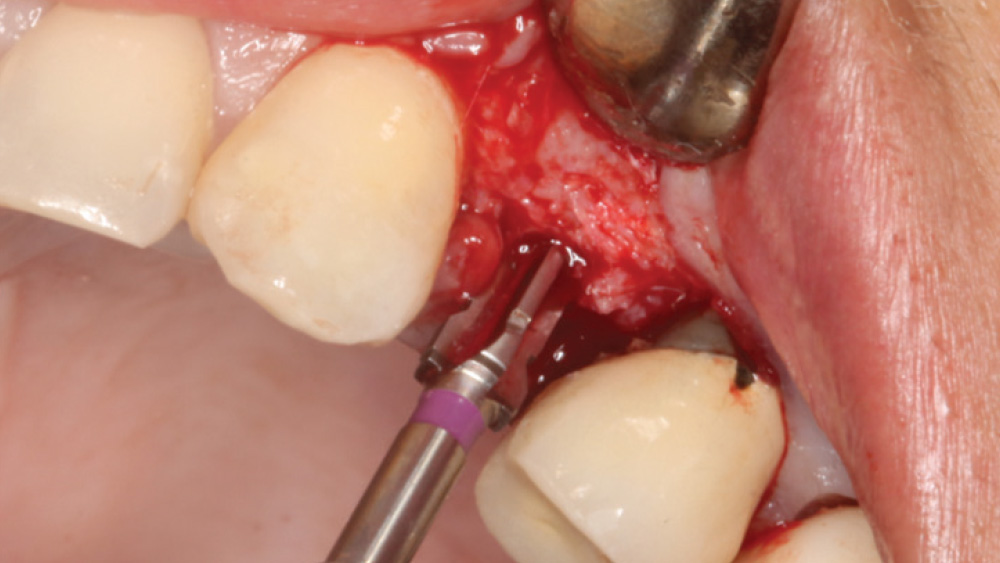

When the attached tissue is minimal, a flap procedure allows the surgeon to reposition the flap to create more attached gingiva and improve the interdental papillae at the implant site. Reflecting a gingival flap also enables the practitioner to more clearly see the final position of the implant at the crest of the bone. If it’s necessary to visualize the bone during the surgical procedure due to uncertain ridge width or height, flap reflection is the safest, most predictable approach.

The following case, which I performed alongside Dr. Stephanie Tilley of Pensacola, Florida, illustrates the use of both surgical techniques for the same patient, who presented with edentulous spaces in the areas of both right and left maxillary first bicuspids. Due to varying soft-tissue volume on each side of the arch, implant surgery was performed using a flapless procedure for one site, while the attached gingiva was reflected to expose the available hard tissue for the other. As a result of proper site evaluation, treatment planning and restorative-driven implant placement, both surgical techniques led to successful outcomes for the patient.